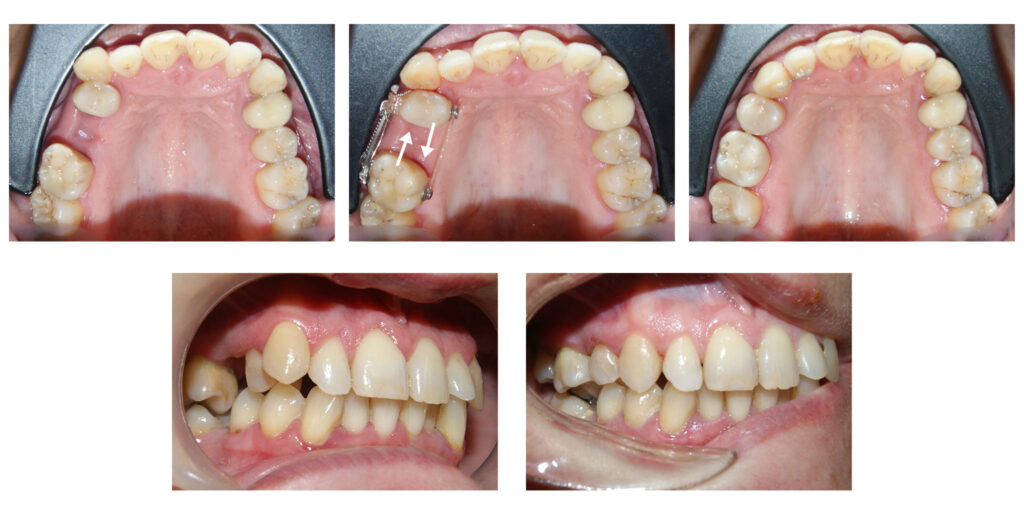

Extruzia ortodontică a dinților cu distrucție subgingivală accentuată salvează unii dinți de la extracție…pentru că dintele natural este cel mai bun implant. Săgețile evidențiază cât de multă extruzie am reușit să obținem în câteva luni.

Redeschiderea spațiilor pentru caninii definitivi (a se observa că pe o parte spațiul era închis complet)

Recâștigarea spațiilor pierdute pentru dinții numerotați cu 2 si 11. Dacă nu am fi pus aparatul ortodontic fix dinții ar fi rămas blocați în intriorul osului, cu consecințe dramatice